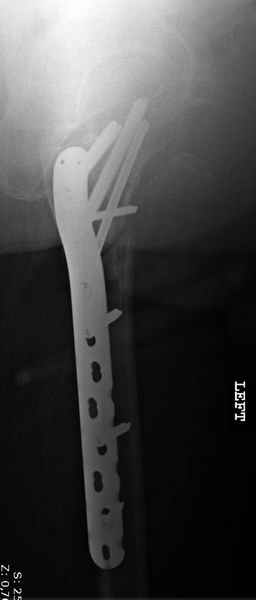

Применили проксимальную Synthes Locking plate, из-за множественных фрагментов посчитали более приемлемым в этом случае (клиника университетская, резиденты должны имет возможность созерцать разные варианты остеосинтеза).

Также старался минимизировать доступ на уровне перелома с субвастус доступом, диафиз фиксирован перкутанно, не стали гонятся за малым вертелом, как смог зафиксировал.